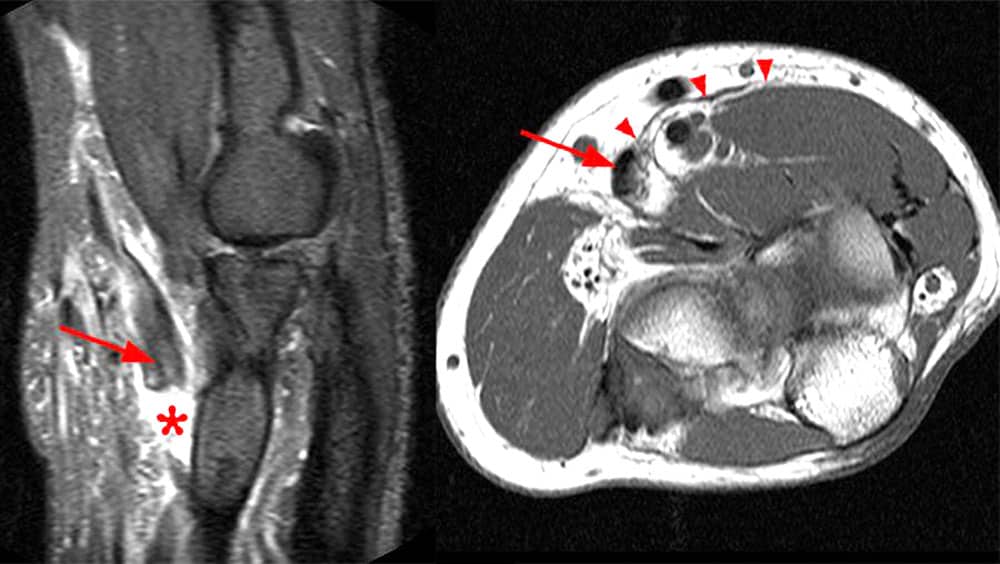

L’échographie ou mieux l’IRM permet de préciser l’étendue de la rétraction et l’état du muscle.